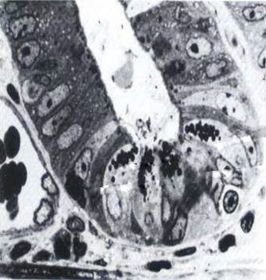

TEM of the basal part Of the crypts Of small intestine

A : Paneth cell B : Apical granules C: Entero-endocrine cell B : basal granules D : blood capillary